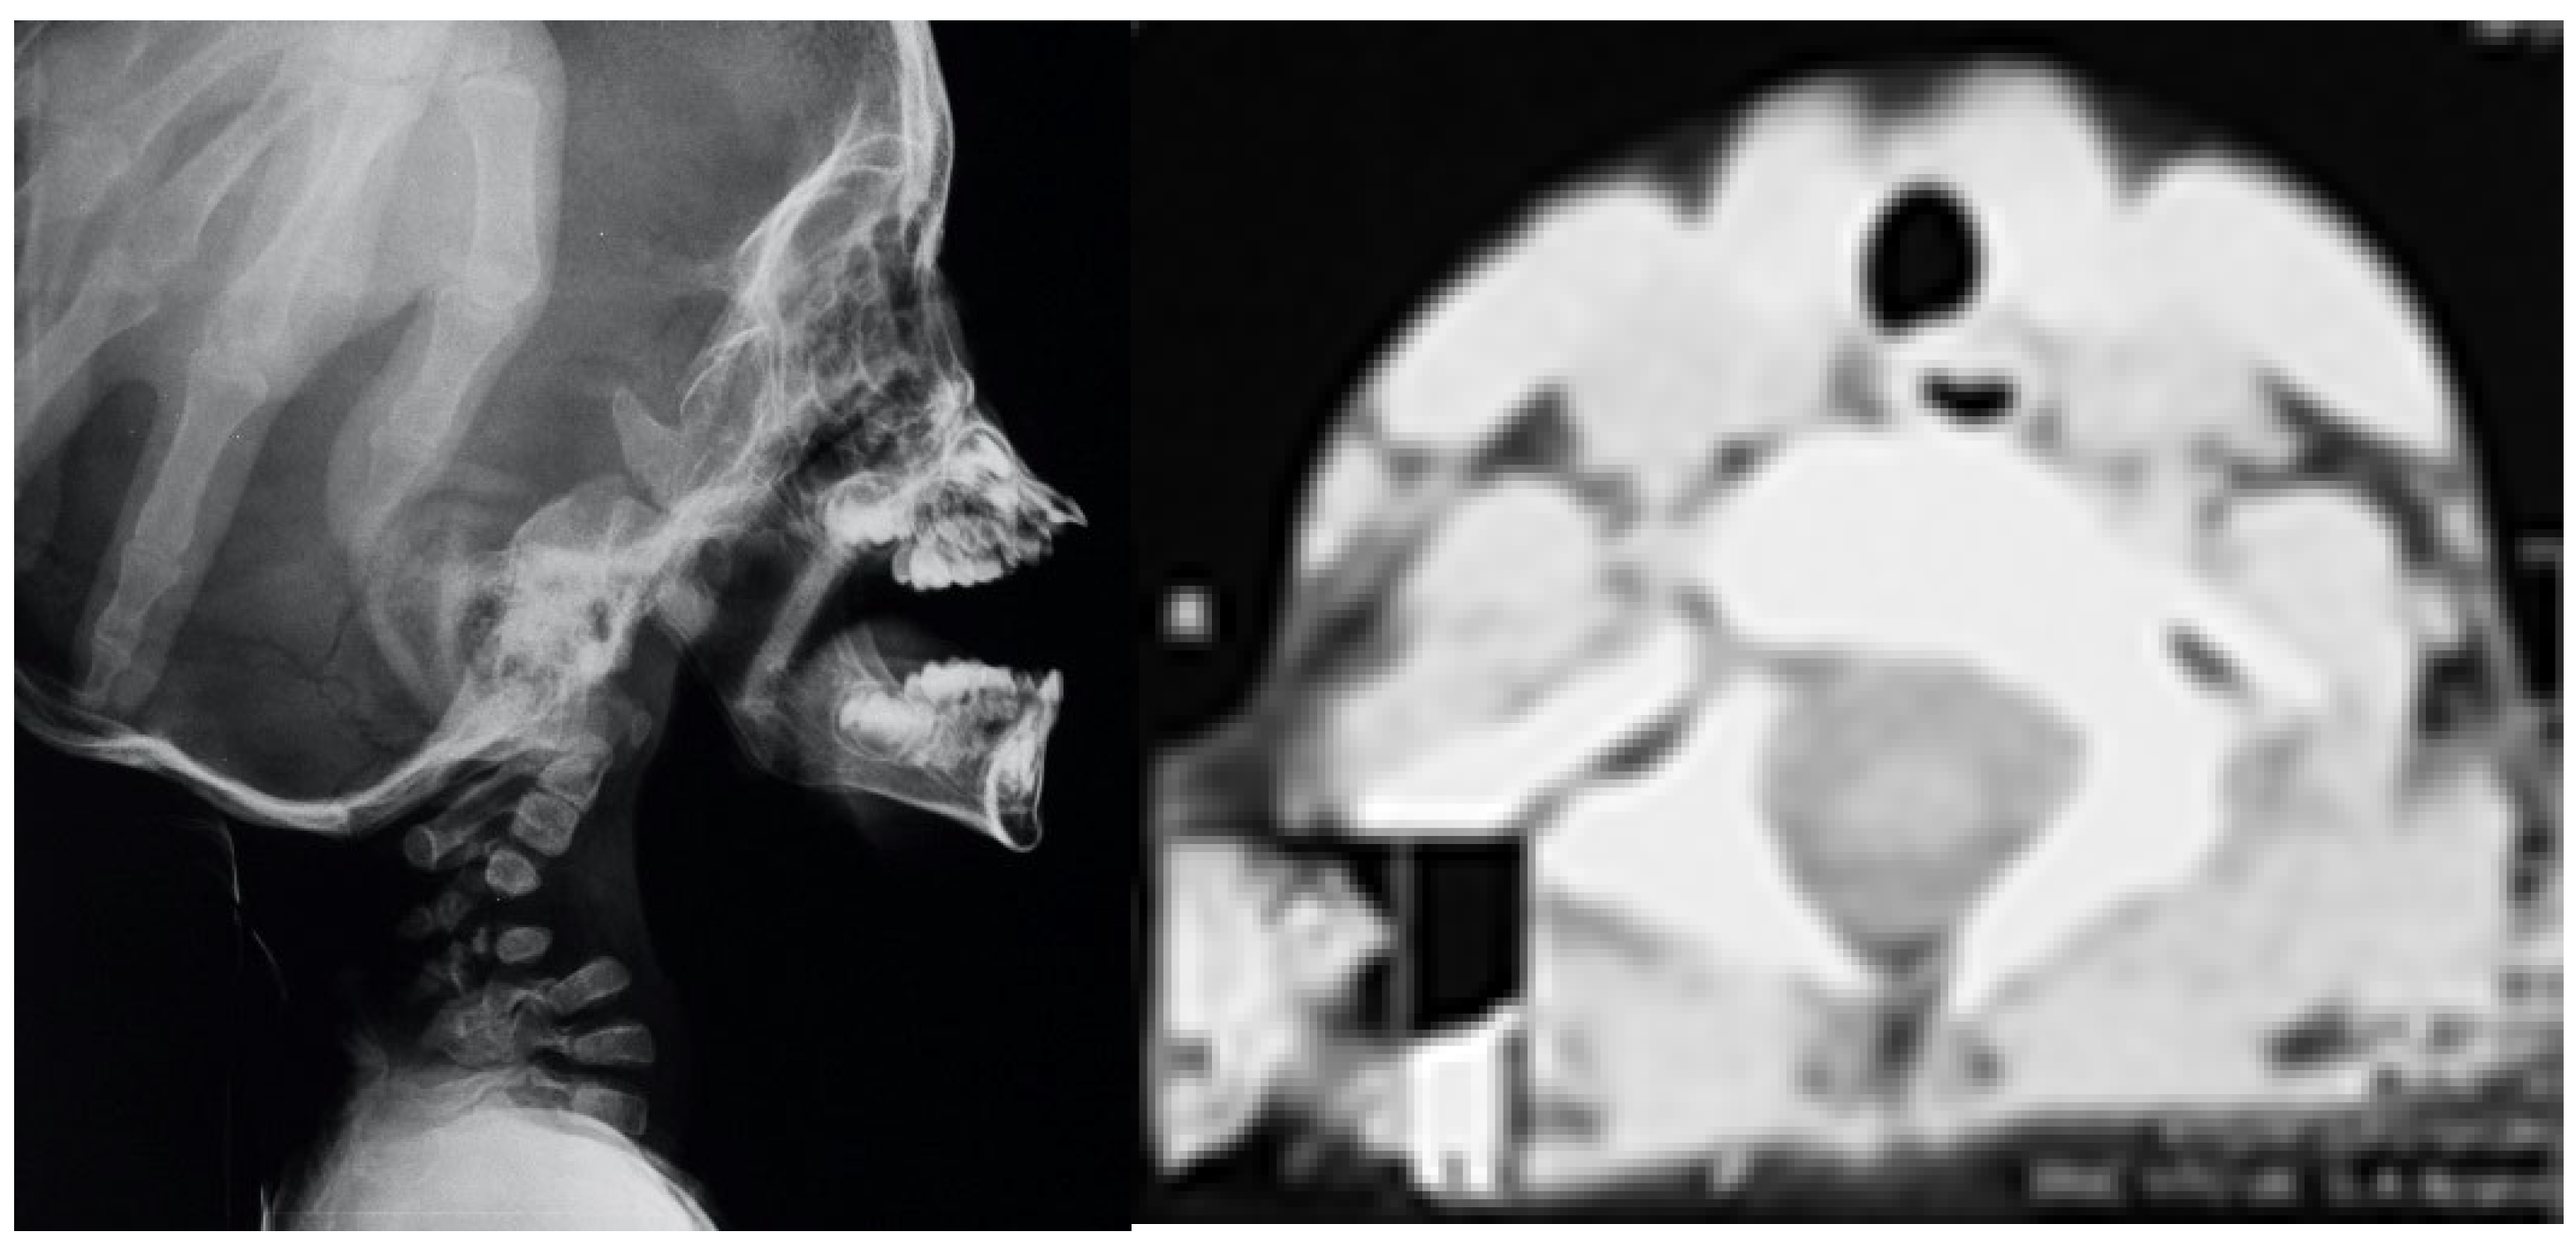

3.2. Congenital Tetraplegia in A Child with Larsen Syndrome

3.3. Acute Angled Kyphosis in A Child with Larsen Syndrome

4. Discussion